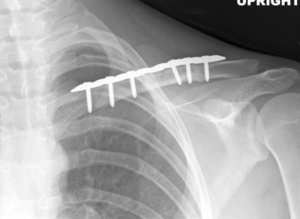

Dr. Riehl treats orthopaedic conditions both operatively and nonoperatively and performs a wide array of orthopaedic procedures including, but not limited to, the following:

Acute fracture care of the pelvis and the extremities